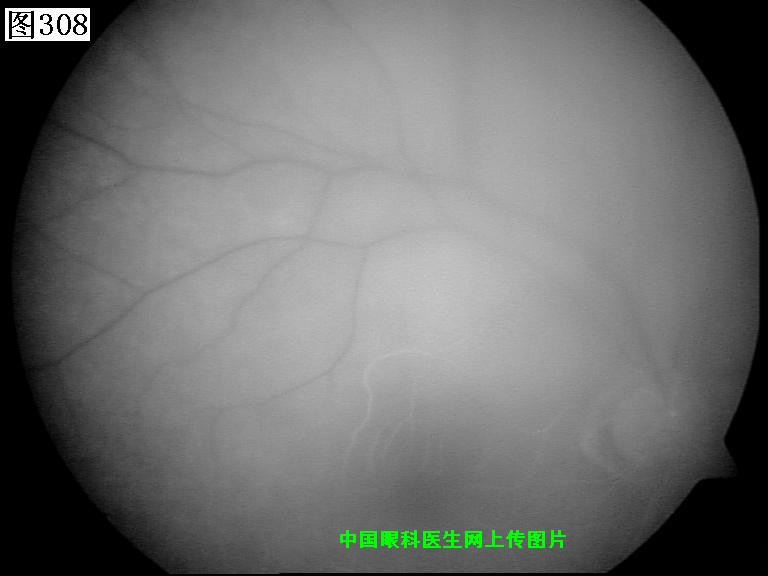

305 306 307 308